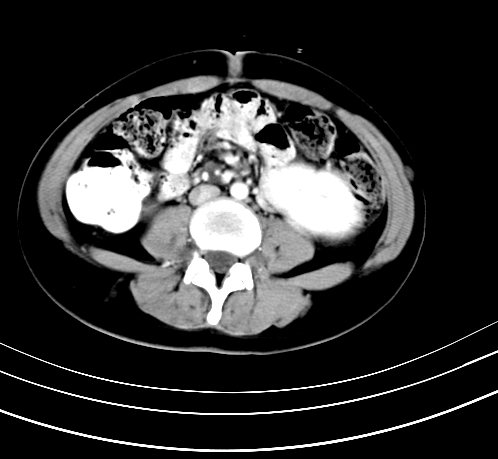

腹部平扫

动脉期

静脉期

延时5分钟

延时10分钟

重建